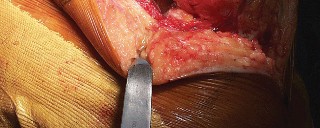

هذه الجراحة ليست مجرد استبدال للمفصل التالف، بل هي عملية تصحيحية شاملة تهدف إلى إعادة المحاذاة الطبيعية للركبة والتخلص من الانحراف التقوسي الذي يسبب الألم ويُسرّع من تدهور المفصل. بفضل الخبرة الواسعة للأستاذ الدكتور محمد هطيف التي تمتد لأكثر من عقدين من الزمن كأستاذ جامعي وجراح عظام متخصص، وباستخدامه لأحدث التقنيات الجراحية مثل الجراحة المجهرية وتنظير المفصل بتقنية 4K وزراعة المفاصل المتقدمة، يتمكن مرضى خشونة الركبة التقوسية في صنعاء من استعادة حركتهم الطبيعية والعيش بلا ألم.